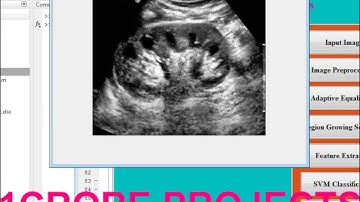

Matlab code for Abnormality detection in kidney ultrasound imaging